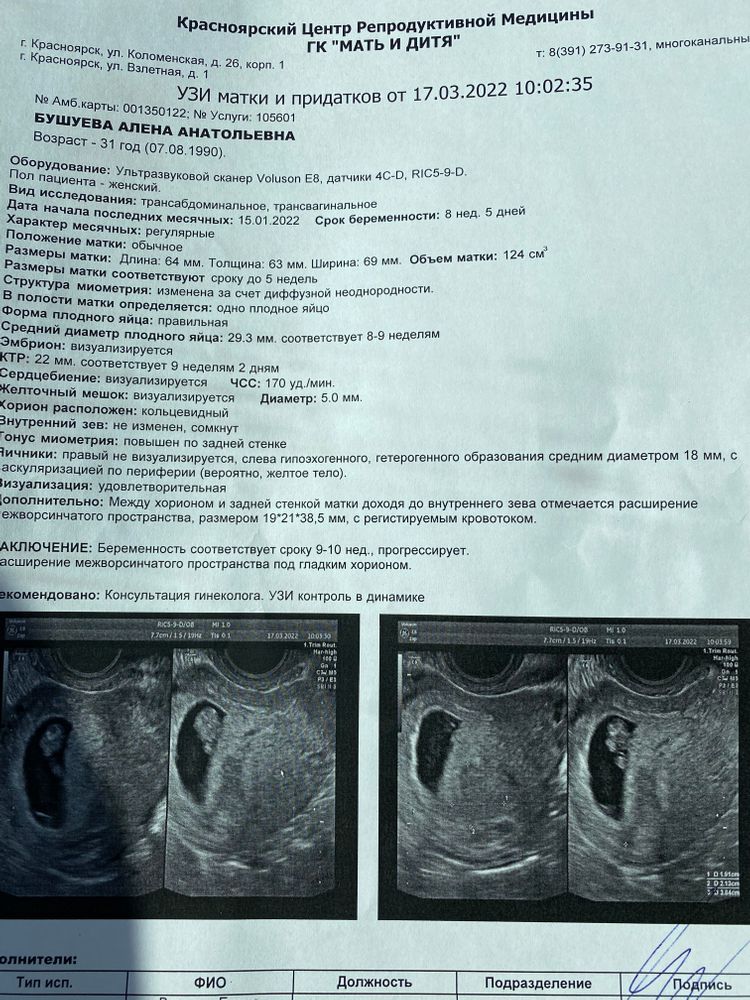

Поход на узи на сроке 8 +5

Так по показателям все не плохо, а узист сам не сказал, что это может значить? Может гематома образовывается из за тонуса.